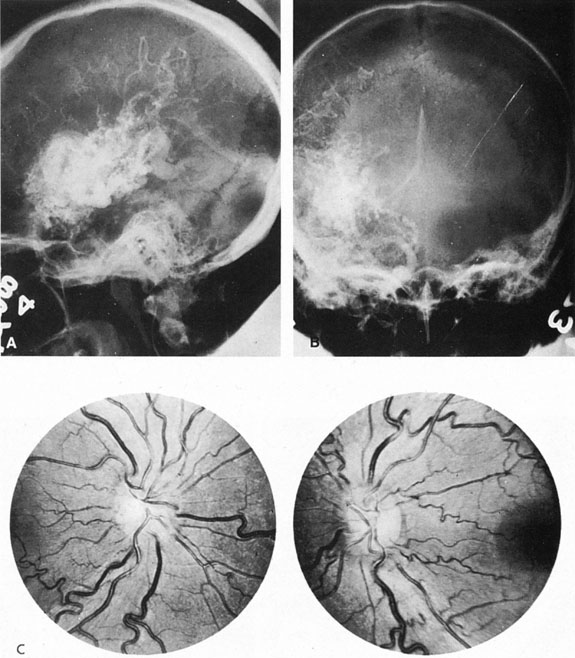

Approximately 100 years ago, Terson recorded the occurrence of vitreous hemorrhage after spontaneous subarachnoid bleeding. Such ocular hemorrhage is believed to result from transmission of intracranial pressure through the subarachnoid communication between the optic nerve sheath and the intracranial cavity, with subsequent nerve sheath dilation and rupture of dural and bridging vessels (Fig. 2). Intraocular hemorrhage is possibly the result of retinal venous hypertension brought on by obstruction of both the central retinal vein and the retinochoroidal anastomoses. Kuhn et al3 have reviewed Terson's syndrome, including the role of pars plana vitrectomy; these authors noted the high incidence of preceding coma, and the efficacy of surgical intervention in visual recovery.

Fig. 2. Terson's syndrome. Multiple preretinal hemorrhages accompanying subarachnoid bleeding.

SUPRATENTORIAL

From 85% to 90% of AVMs are in the supratentorial compartment and are supplied primarily by the carotid circulation (Figs. 7 and 8). The remainder are supplied by the vertebrobasilar system. The approximate frequency of location is as follows: frontal, 22%; temporal, 18%; parietal, 27%; occipital, 5%; and deep intraventricular or paraventricular, 18%. The intracerebral site of the malformation does not necessarily indicate that there will be signs referable to that area simply from the mass effect of the malformation. Clinical features primarily result from subarachnoid hemorrhage or intraparenchymal hemorrhage with hematoma formation.

Fig. 7. Supratentorial arteriovenous malformation in a 28-year-old woman with a history of focal motor seizures for many years and a recent subarachnoid hemorrhage. A: Lateral projection carotid arteriogram demonstrating a huge deep hemispheral arteriovenous malformation. B: Frontal projection. C: Fundus photograph showing anomalous tortuous vasculature in each eye. No retinal arteriovenous shunt was detectable.

The detection of intracranial AVMs is facilitated by CT scanning and MRI (Fig. 10),88 but optimal management requires selective angiography89 that assesses the size and configuration of the mass, the number and location of feeding arteries, the flow characteristics and degree of steal from brain parenchyma, and the pattern of venous drainage.

Fig. 10. Neuroimaging of arteriovenous malformation. A: Coronal magnetic resonance imaging (MRI) (TR, 600 ms; TE, 20 ms) shows wedge-shaped vascular mass extending from the surface of the parietal cortex (white arrows) to the lateral ventricle (black arrows; asterisk, arterial feeder). B: Posteroanterior left arteriogram of the same lesion. C: Axial computed tomography scan with contrast enhancement. D: Axial MRI of a large arteriovenous malformation, first echo (TR, 2000 ms; TE, 20 ms). E: Second echo (TR, 2000 ms; TE, 90 ms). (From Smith HJ, Strother CM, Kikuchi Y, et al: MR imaging in the management of supratentorial intracranial AVMS. AJNR Am J Neuroradiol 9:225, 1988.)